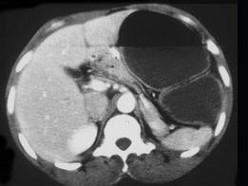

男,23岁,急性左上腹痛,腹胀,结合图像,应考虑为 ( )A、小肠梗阻B、肠套叠C、胃扭转D、结肠梗阻E、结肠扭转

问题 男,23岁,急性左上腹痛,腹胀,结合图像,应考虑为 ( )

选项 A、小肠梗阻 B、肠套叠 C、胃扭转 D、结肠梗阻 E、结肠扭转

答案 E